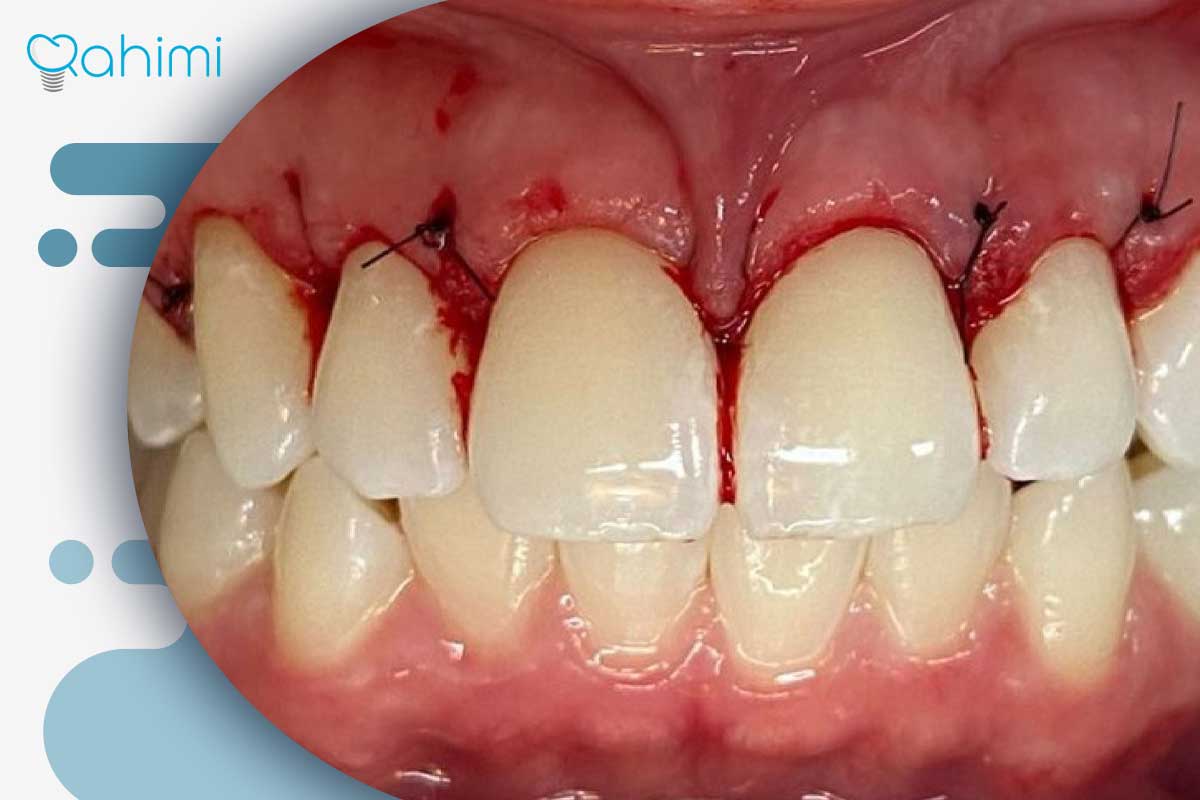

| پیوند لثه (Gum Graft) | بازسازی بافت لثه و پوشاندن ریشه | - برداشتن بافت از سقف دهان یا اطراف- قرار دادن و بخیه بافت در ناحیه تحلیل رفته یا سوراخ- افزایش ضخامت لثه، پوشش ریشه و اصلاح حفره- بهبود سلامت و زیبایی لبخند |

| جراحی فلپ و ترمیم پاکتهای عمیق | برداشتن جرم و بافت ملتهب و ترمیم استخوان | - کنار زدن کنترلشده لثه- حذف جرم، بافت ملتهب و ضایعات عفونی- ترمیم نقصهای استخوانی با مواد پیوند- بخیه لثه در محل مناسب- کاهش عمق پاکت و حذف یا کاهش حفرههای عمیق |